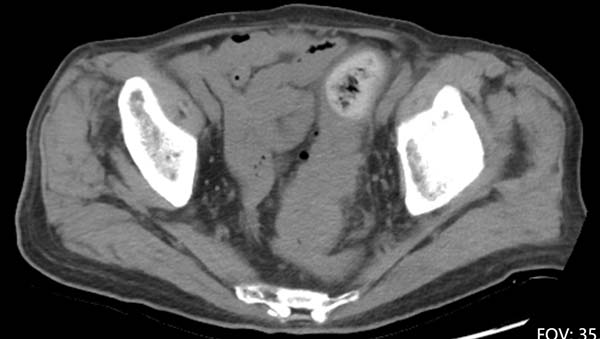

腹盆腔平扫CT显示直肠乙状结肠连接部巨大占位伴周围渗出